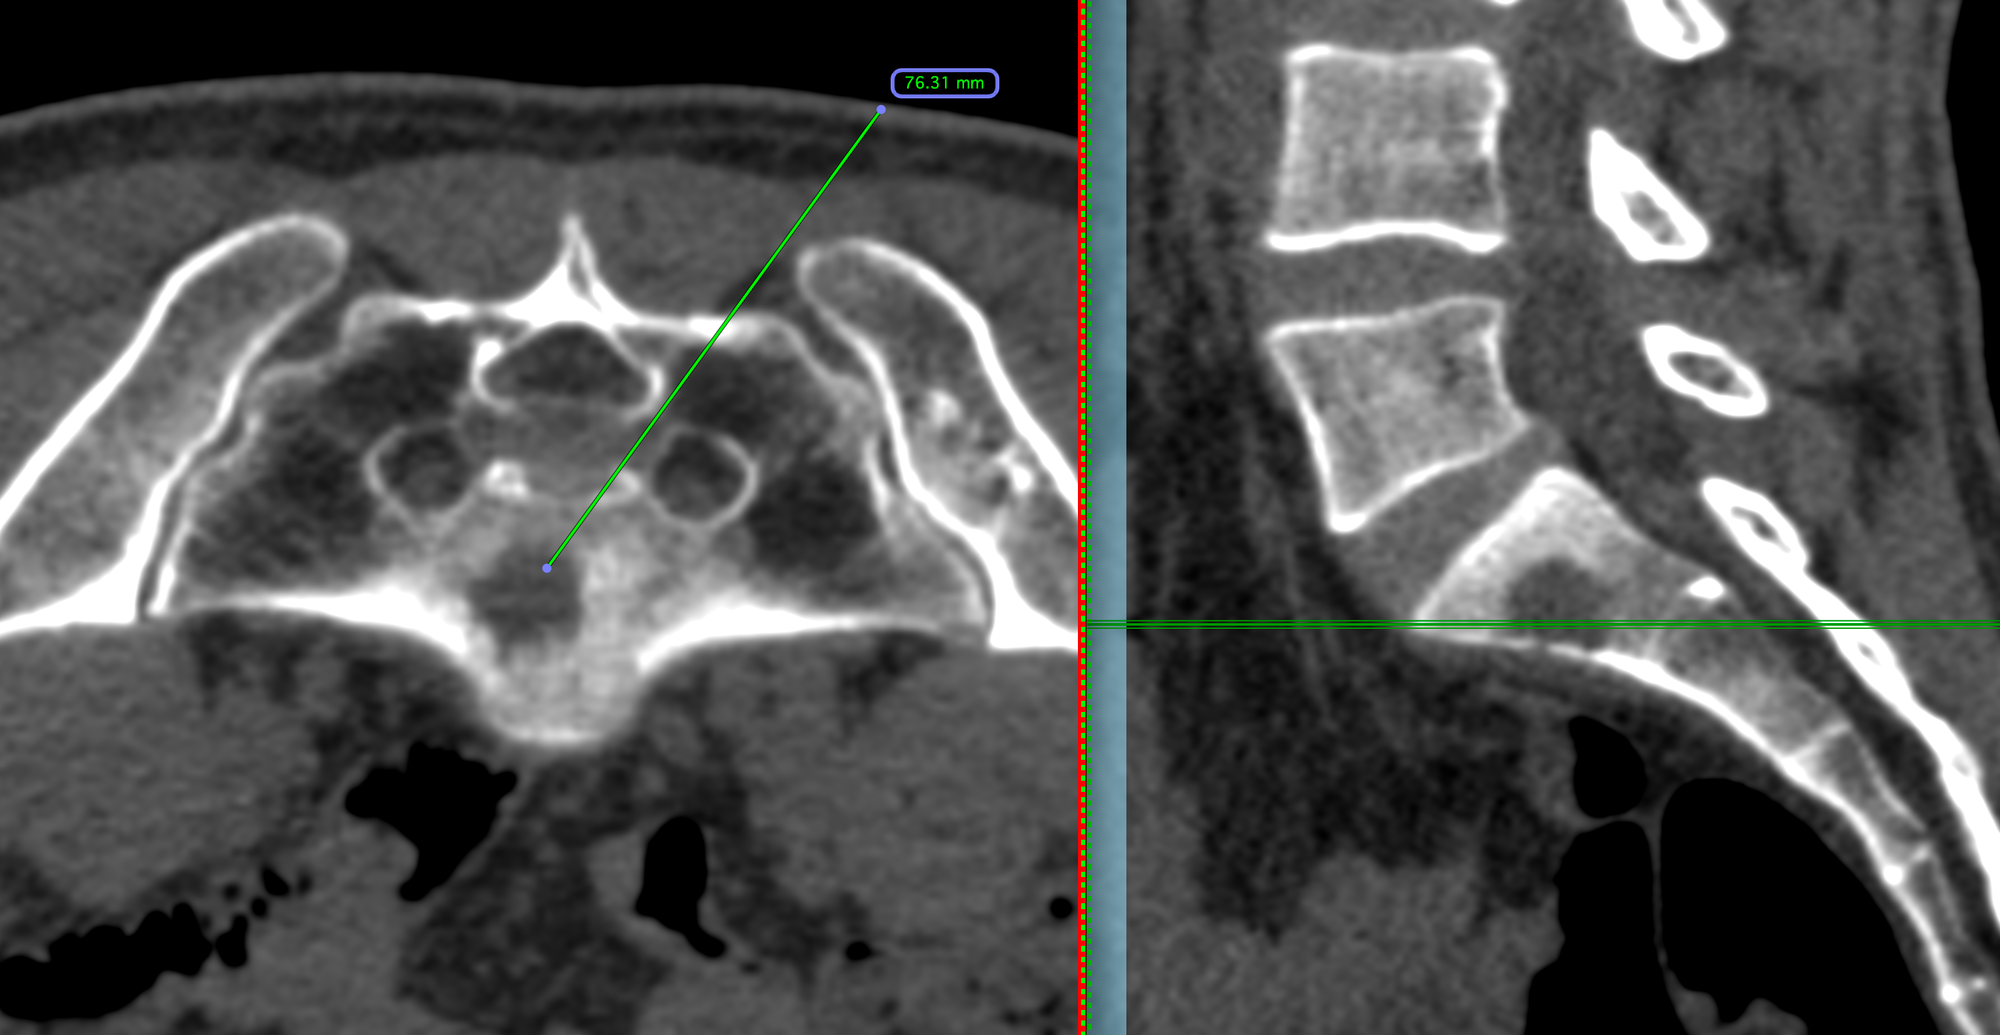

43-years old treated buccal ca had progressive lung and nodal lesions (arrow in to panel), stable liver lesions and a new S1 osteolytic lesion on PET (arrow in bottom panel) (Fig. 1).

The patient was referred for a CT guided biopsy of the sacral lesion.